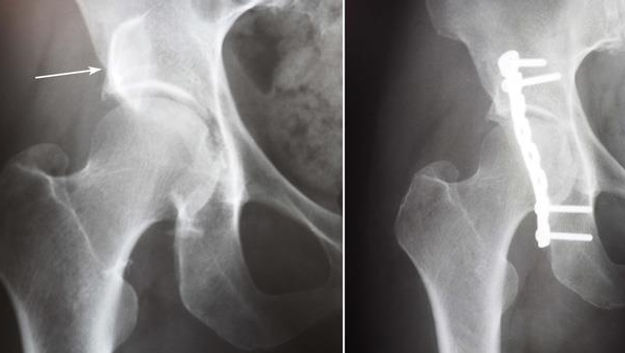

An acetabular fracture is a break in the socket portion of the "ball-and-socket" hip joint. These hip socket fractures are not common they occur much less frequently than fractures of the upper femur or femoral head (the "ball" portion of the joint).

Treatment for acetabular fractures often involves surgery to restore the normal anatomy of the hip and stabilize the hip joint.

If the femur head is dislocated, it should be reduced as soon as possible, to prevent damage to its blood supply. This is preferably done under anesthesia, following which, leg is kept pulled by applying traction to prevent joint from dislocating. Surgical fixation using screws and plates may be required if the injury is complex.